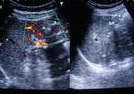

入院查体: 血压18/13kPa,神经系统(—).测血清微量元素均在正常范围,血皮质醇、醛固酮和24h尿VMA均正常.术前CT 诊断:左肾上腺肿瘤,腺瘤可能性大术中见左肾上腺结构正常, 未见占位性病变,紧贴左肾上腺可见一大小约1cm×1.5cm实性物质,呈暗红色,行肿物切除术术后病理:副脾。

诊断:考虑左肾上腺肿瘤,腺瘤可能性大 治疗:术中见左肾上腺结构正常, 未见占位性病变,紧贴左肾上腺可见一大小约1cm×1.5cm实性物质,呈暗红色,行肿物切除术术后病理:副脾。

随访:未完成 讨论:在脾的附近,尤其是在胃脾韧带内和大网膜内,有时会发现一些具有被膜的小结节状脾组织,它们或为单个,或以细条状脾组织与脾相连,这就是副脾。副脾的数量有时可能相当多, 而且可能会在腹腔内呈弥散分布。当副脾与肾上腺位置贴近时,易被误诊为肾上腺肿物,尤其当患者临床有高血压症状时,更会想到腺瘤的可能。但本例患者没有低血钾及周期性麻痹症状,是与腺瘤诊断不相符的,应诊断为原发性高血压。由于这种情况极少见,一般不会想到是副脾。可疑时应行增强扫描,若发现结节与脾脏同时强化,则有助于副脾的判断。另外,若为副脾时同侧肾上腺应为正常形态,而为腺瘤时残余肾上腺常有萎缩改变。